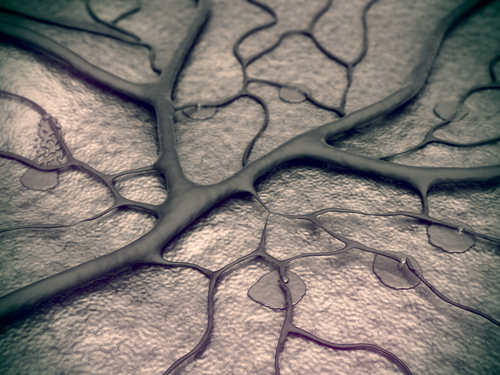

A team of researchers from Johns Hopkins Medicine (Baltimore, MD) has discovered a receptor on blood vessels that causes the vessel to relax in response to blue light, making it potentially useful in treating vascular diseases.

The researchers—led by senior author Dan Berkowitz, MD, a professor in the Department of Anesthesiology and Critical Care Medicine—looked for expression of a light receptor in the blood vessels of mice and discovered a receptor called melanopsin, or opsin 4—one of a group of non-image-forming light receptors. In mice without opsin 4, blood vessels did not relax in response to light.

Upon further study, Berkowitz and his team were able to determine the exact wavelength (455 nm) at which opsin 4 is activated and the blood vessel relaxation response is maximal. The scientists could use this wavelength-specific light to increase blood flow in the tails of normal mice, but not in the tails of mice that lacked expression of opsin 4.

(Thumbnail image via Shutterstock)